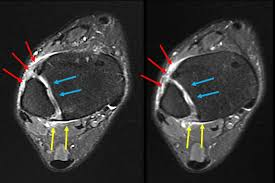

- Aa tendinopatia insercional, aquela que acontece na região onde o tendão se insere no osso e a não insercional, que está relacionada a inflamação e degeneração no corpo do tendão, como mostram as imagens de ressonância magnética na figura abaixo. A tendinopatia insercional tende a ocorrer em pessoas mais ativas

Figura 1: Imagem de ressonância demonstrando da esquerda para a diretia: imagem com tendão normal, imagem com tendinopatia insercional e imagem com tendinopatia no corpo do tendão de aquiles.